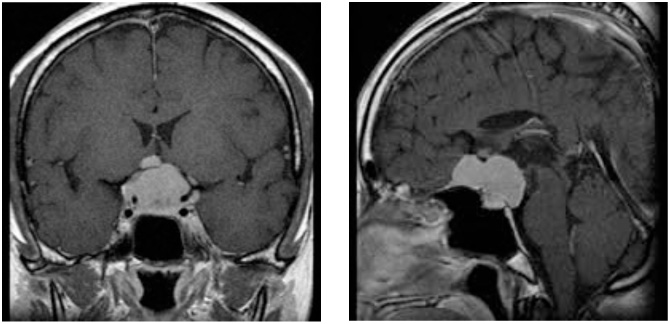

図2 頭蓋底髄膜腫 48歳女性 歩行障害、嚥下困難で来院

術後MRI:海綿静脈洞への浸潤部を除き

摘出、歩行障害改善し退院